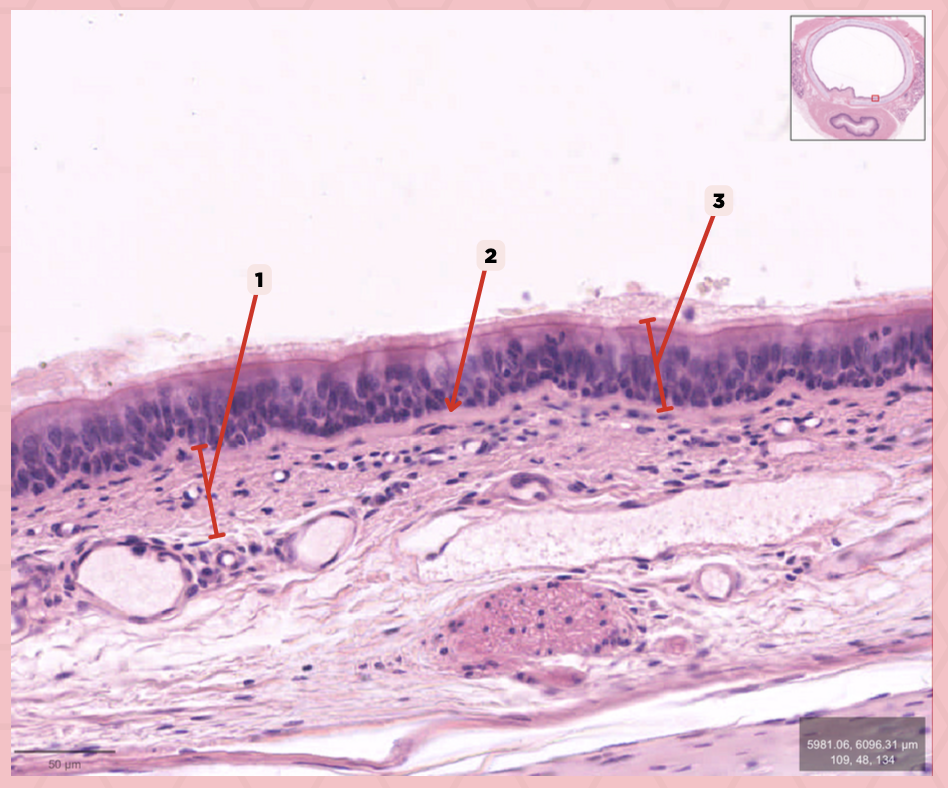

Lamina Propria

Identify the structure labeled as 1.

Basement Membrane

Identify the structure labeled as 2.

Respiratory Epithelium

Identify the structure labeled as 3.

Tracheal glands

What glands are found in no. 2?

Mixed Tubuloalveolar Glands

Specify the type of glands are tracheal glands.